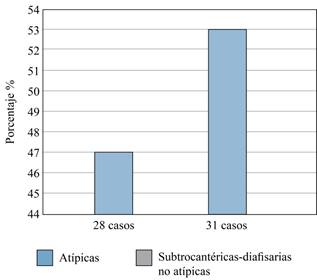

Una vez realizada dicha clasificación, se analizaron únicamente las fracturas de fémur subtrocantéricas (FS) y diafisarias (FD); y se aplicaron los criterios de la American Society for Bone and Mineral Research para la definición de caso de «fractura atípica de fémur» (FAF) en cada uno de los registros, por tres investigadores diferentes, realizando consenso en aquellos casos que existía diferencia de criterio. De tal forma se conformaron dos grupos: «fracturas atípicas de fémur» (FAF) y «fracturas diafisarias/subtrocantéricas de fémur» (FD/FS) (Figura 2).

Se analizó un total de 441 registros clínicos, de los cuales 98 (22.2%) eran del sexo masculino y 343 (77.7%) del femenino. Posterior a la revisión de los estudios radiológicos y clasificación de la ubicación de las fracturas en el fémur, se constató un total de 51 FS/FD. Tras la aplicación de los criterios de definición de FAF, se determinó la existencia de 31 casos (Figura 3).